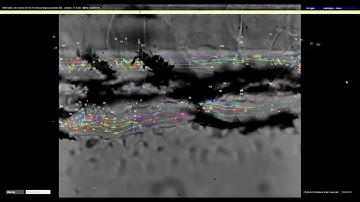

Zebrafish blood flow evaluation using a microscope- MicroZebraLab